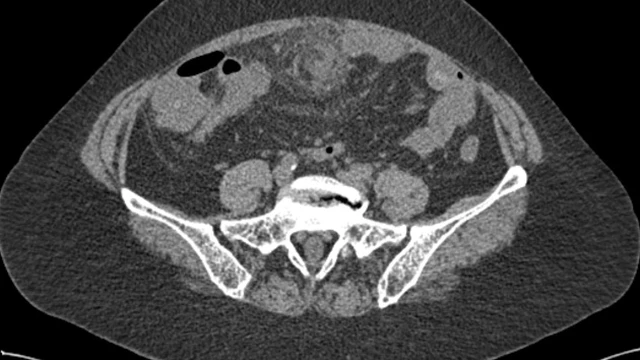

Hoại tử mạc nối lớn là một vấn đề không chỉ gây đau đớn mà còn tiềm ẩn nhiều biến chứng nguy hiểm, như viêm phúc mạc toàn thể, áp xe, và thậm chí tử vong. Trong bài viết này, chúng ta sẽ tìm hiểu về nguyên nhân, triệu chứng và phương pháp điều trị hoại tử mạc nối lớn.